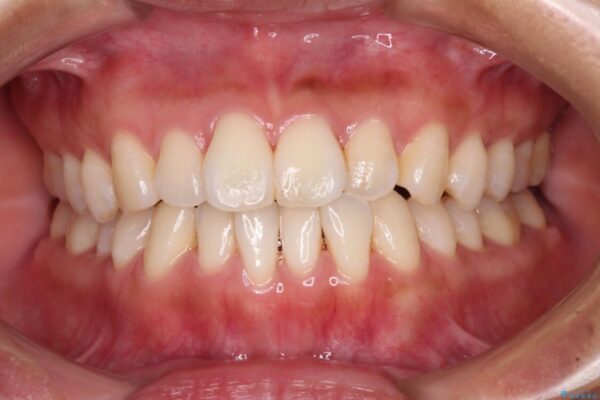

装着時間を守ってくださったので、予定通りの期間で終えることができました。インビザライン特有の、奥歯の咬み合わせの問題もなく、しっかりと歯列を改善することができました。

治療後